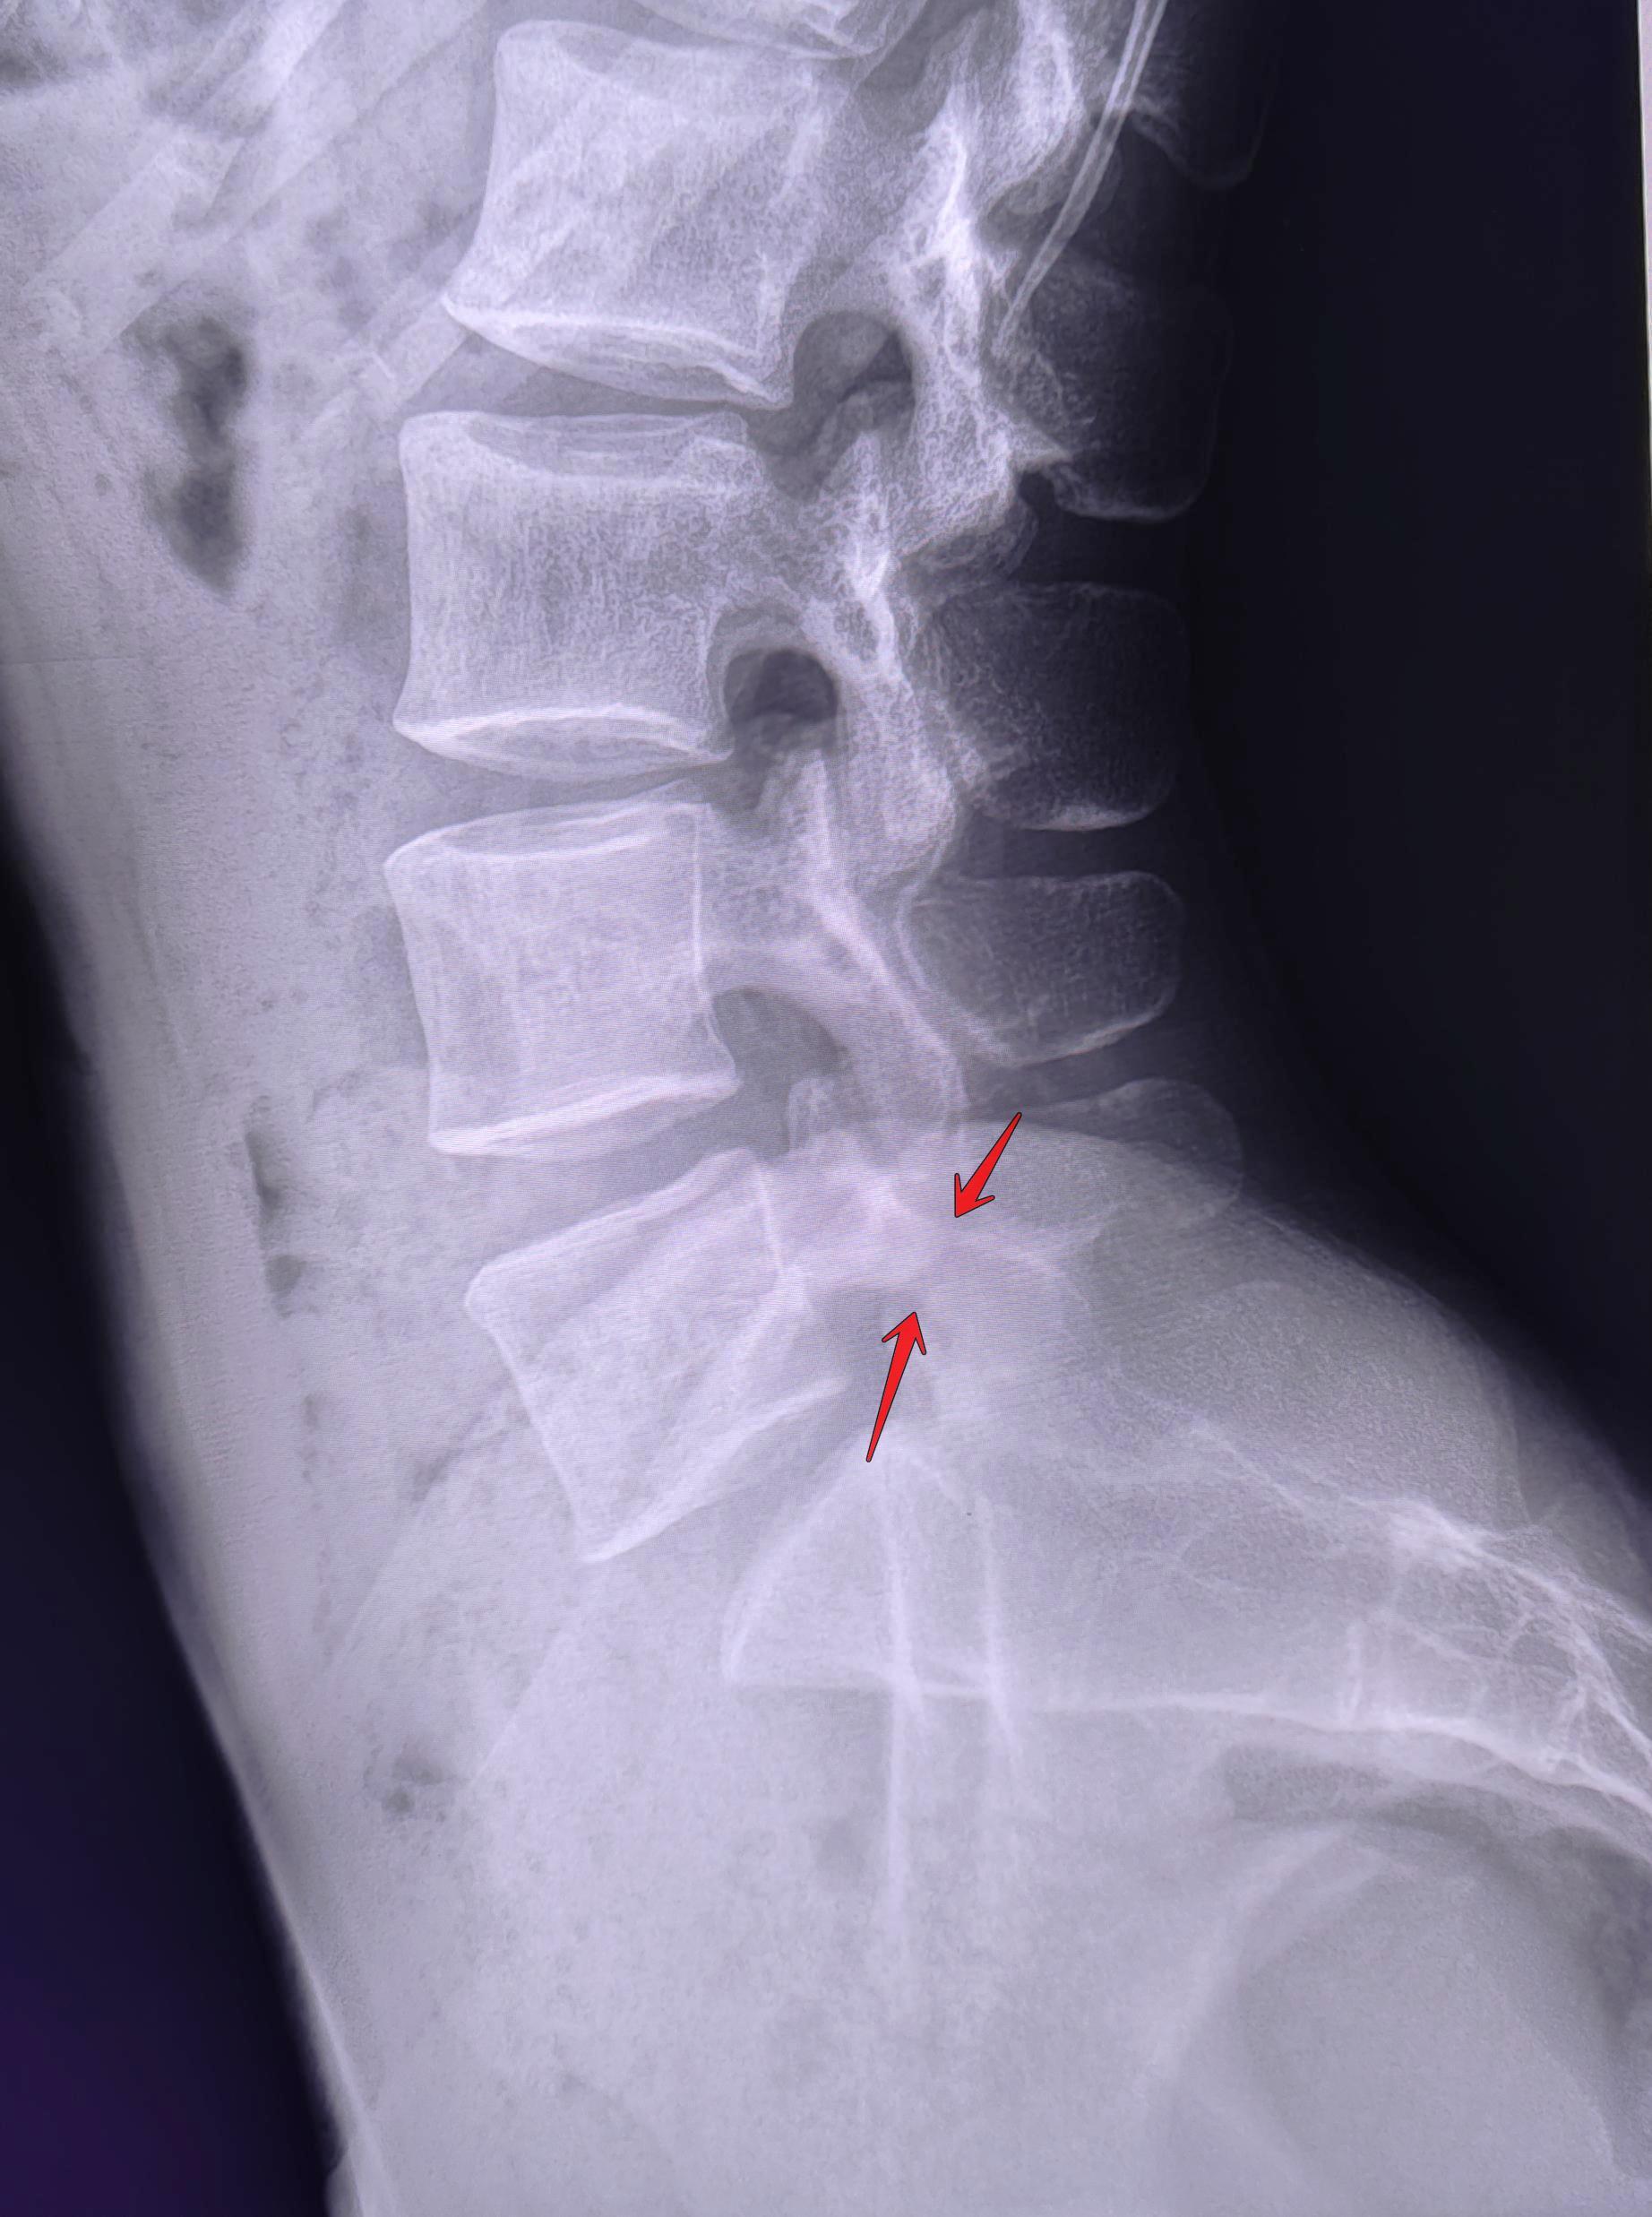

Визуализируется левосторонний дефект дуги L5 позвонка, соотношение задних отделов тел позвонков не нарушено(спондилолистез отсутствует),межпозвонковые щели не сужены, субхондральный склероз замыкательных пластин отсутствует, краевые остеофиты тел позвонков не выявлены. Заключение: Левосторонний спондилолиз L5 позвонка.